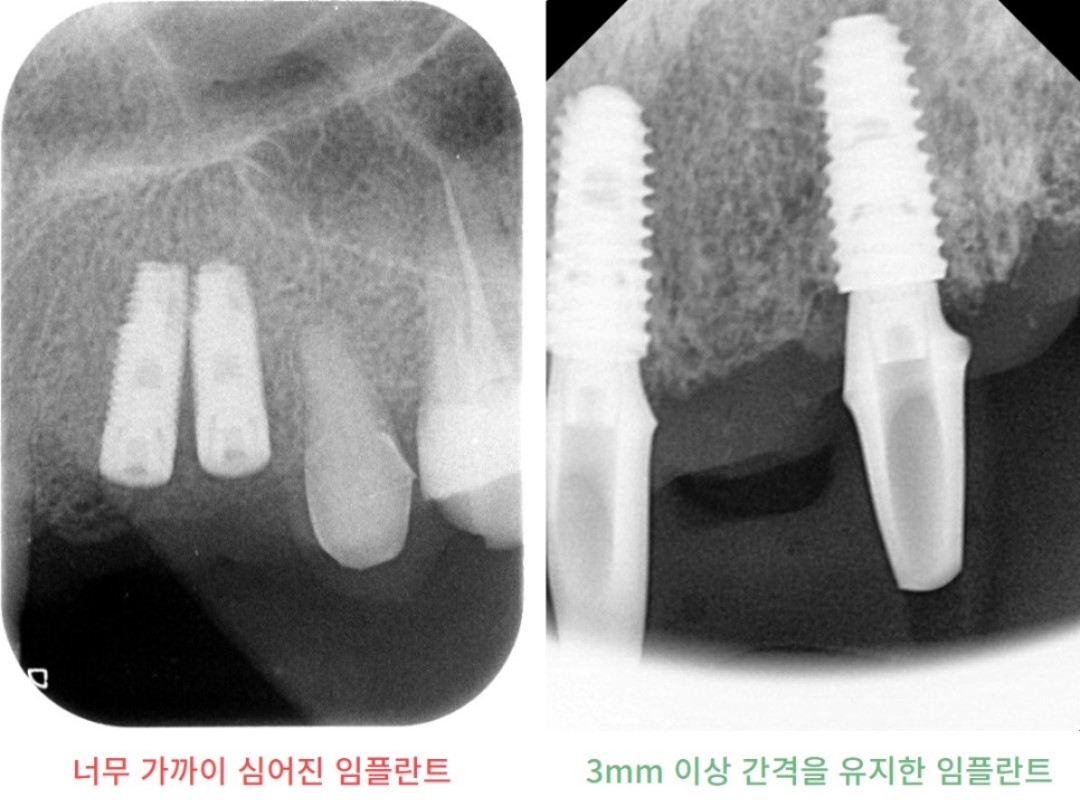

하지만 여기서 주의할 것은, 임플란트 사이 간격이 충분해야 하는데요.

보통은 임플란트와 임플란트 사이 간격이 3mm 정도는 되어야

임플란트가 뼈와 붙는데 무리가 없습니다.

06b0cde33271b.jpg